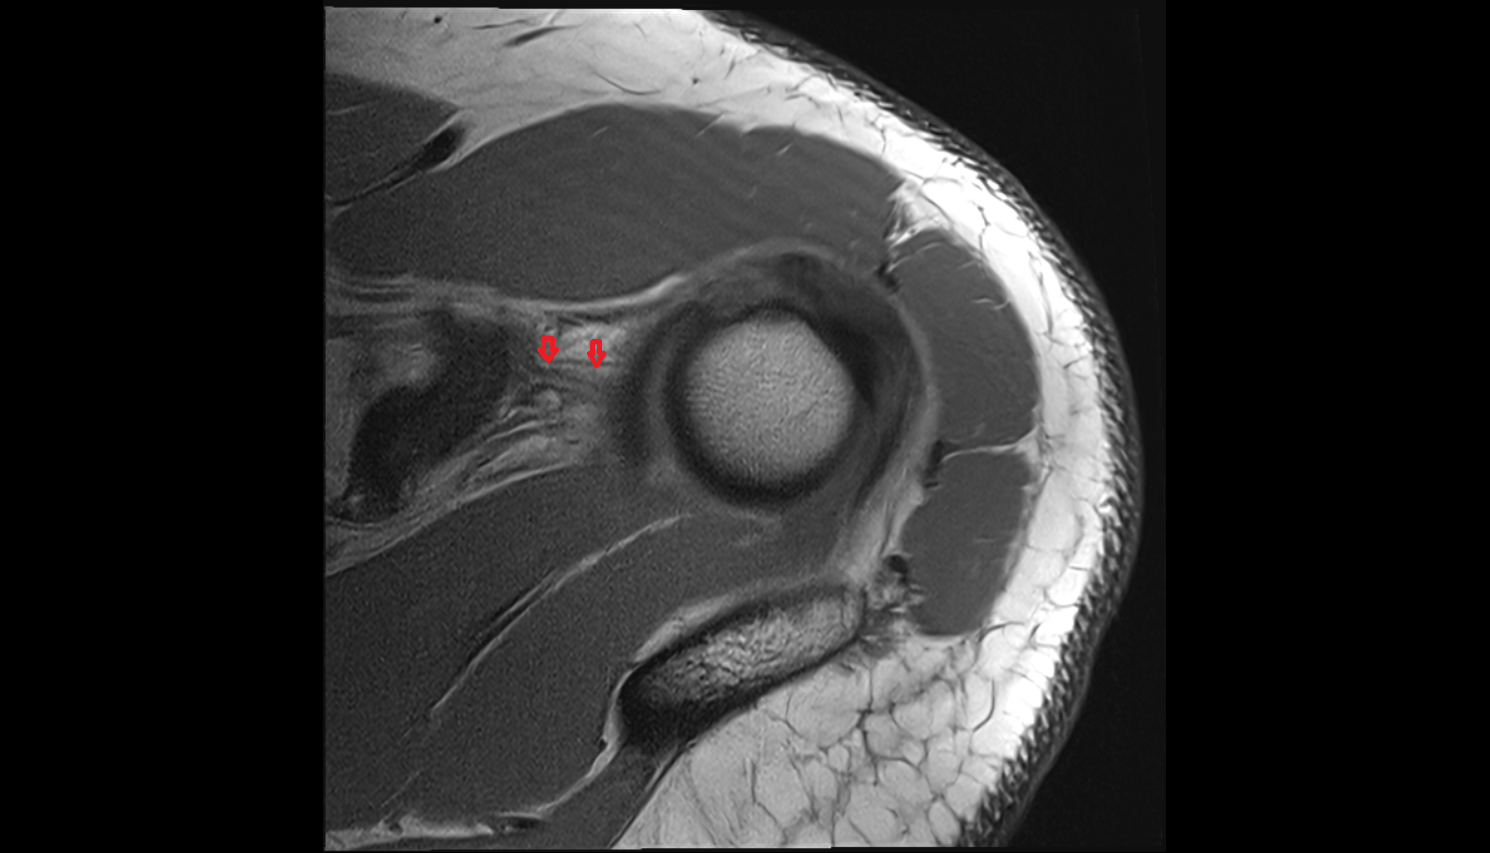

- Shoulder joint (glenohumeral joint)

- Glenoid labrum

- Supraspinatus tendon

- Subscapularis tendon